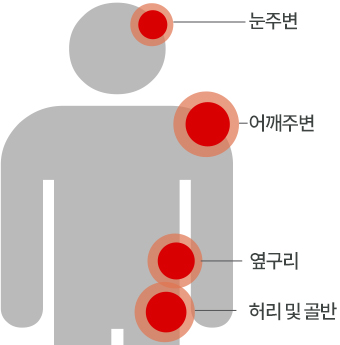

대상포진 주요 발생부위